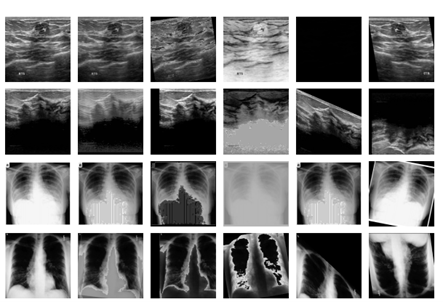

Another key component of preprocessing is data augmentation, which increases the diversity of the training set. In medical segmentation, common augmentations include geometric transformations such as rotations, scaling, and flipping. Intensity augmentations are also frequently applied, including contrast adjustment, brightness modification, and noise simulation.

Figure 2. Examples of augmented medical images. Figure sourced from [2].

[2] Zhaoshan Liua, Qiujie Lvb, Yifan Lia, Ziduo Yanga,c, Lei Shena. (2024). MedAugment: Universal Automatic Data Augmentation Plug-in for Medical Image Analysis.